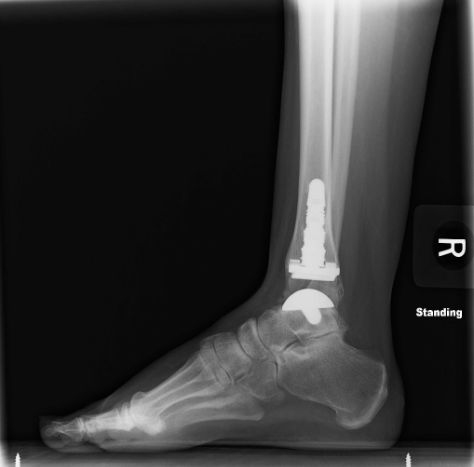

Otherwise know as "ankle arthroplasty," ankle replacement surgery is a technique that has developed in recent years in response to the need to effectively improve an ankle joint that has been severely damaged by injury or some form of arthritis. When other, more conservative methods of treating disabilities in the ankle have proven inadequate, joint replacement surgery may represent the best hope for long-term improvement to the ankle joint.

Both sides of the ankle are removed and replaced with specially designed artificial parts, called prostheses. The tibial prosthesis is made of medical- grade plastic with a titanium base plate tray that is inserted into the tibia and fibula. The talar component of the joint, the part that moves up and down, is replaced with a part made of cobalt chromium alloy, a metal commonly used in prostheses for other joints of the body also.